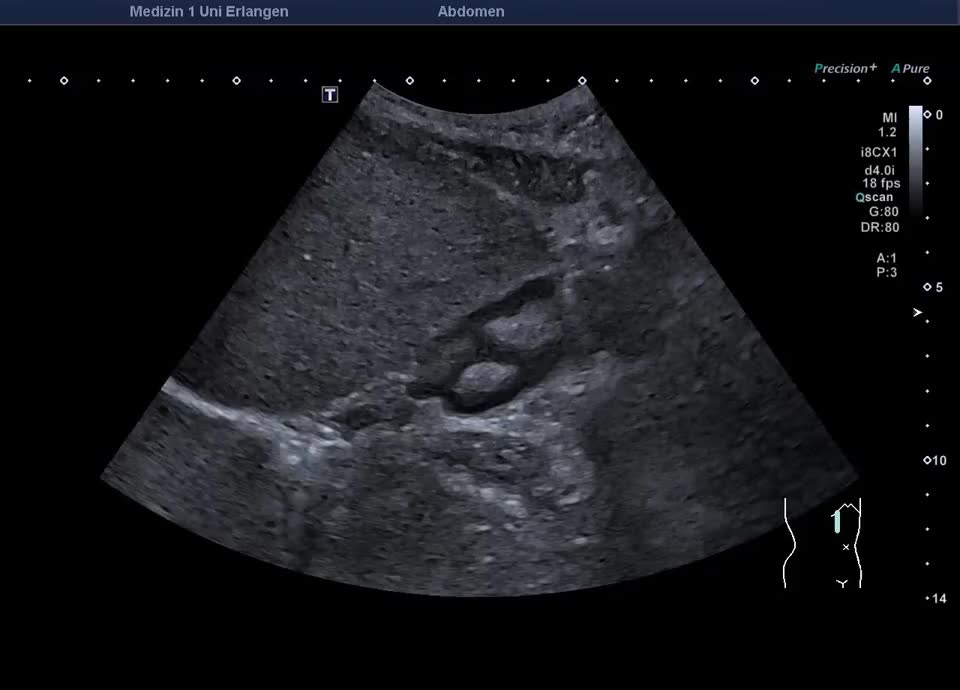

Histologisch gesicherter IgG4-assoziierter Pseudotumor in der rechten Niere

Histologisch gesicherter IgG4-assoziierter Pseudotumor in der rechten Niere (hochfrequenter Linearschallkopf)